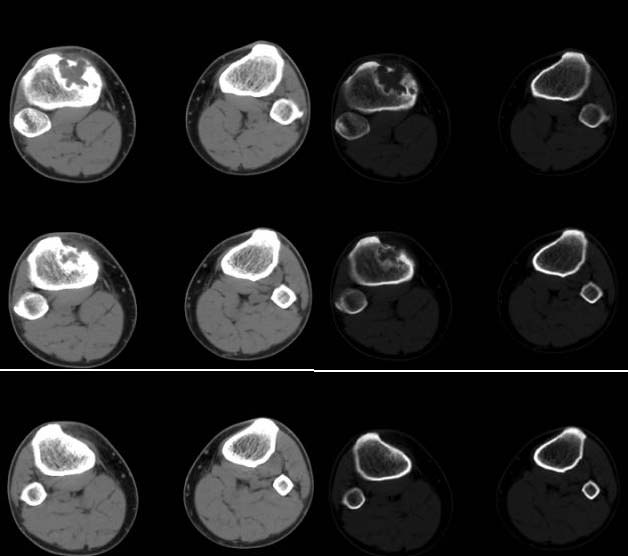

男,38岁,右膝下方剧烈运动后疼痛1年3个月,疼痛加重并局部隆起1个月。查体见轻度跛行,右胫骨近端前内侧轻度隆起,隆起部位压痛明显,皮温略有增高。右膝关节活动度基本正常,麦氏征、膝关节抽屉试验(-)。

胫骨近端、骨骺前内侧见局限性骨质破坏,边缘硬化明显,其间有少许残陈骨,边缘增生硬化,并可见嵴状突起,皮质部分断裂,无骨膜反应。

征象:胫骨上干骺端偏心性类圆形骨质破坏,边缘硬化,可见病理性骨折,内有残留骨嵴。未见明显骨膜反应及软组织肿块。